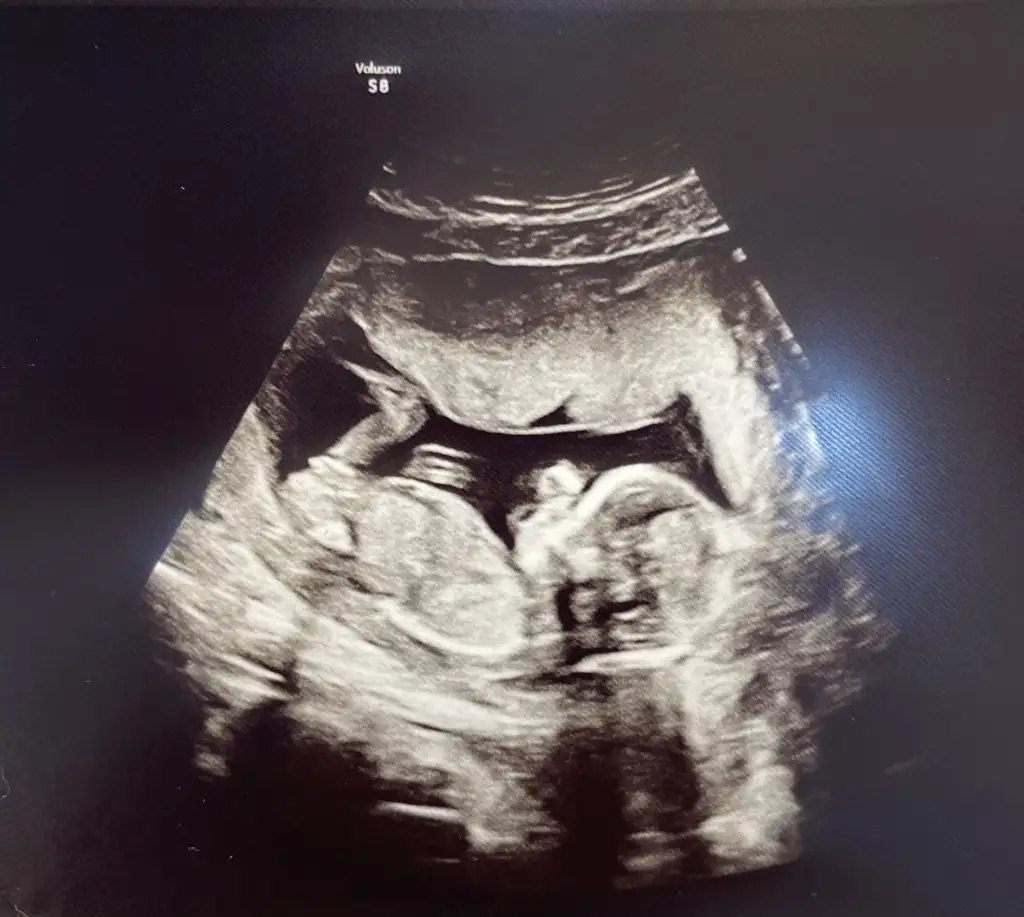

Doktordan çıktım %90 kız dedi. Sonrasında değişme olmaz inşallah herkese söyledik bile 🙈

Sonra döndü sirtustu yatti doktor da 3boyutlu gosterdi bakin bu pipisi bunun donusu yok dedi😄